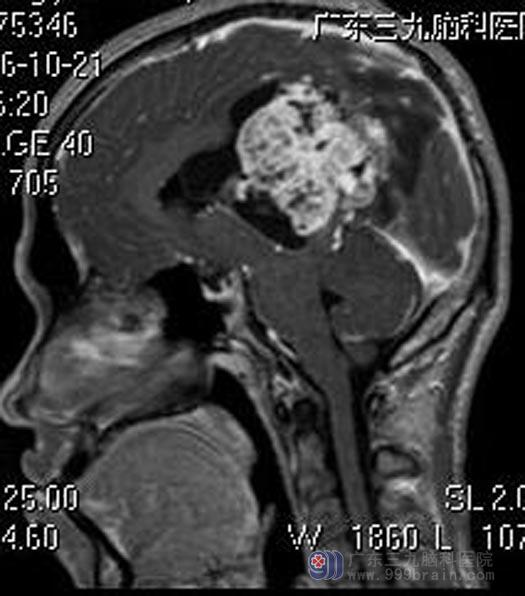

广东三九脑科医院进一步头颅MR检查提示:左侧丘脑-扣带回-侧脑室区示一团块状不规则囊实性占位性病变,病灶跨中线生长,大小约7.3cm×5.9cm×6.3cm,增强扫描病灶实性成分呈明显强化,囊性部分呈囊壁强化,邻近脑组织、脑干受压,首先考虑室管膜瘤或中枢神经细胞瘤,同时需注意脑外病变(囊性脑膜瘤)。